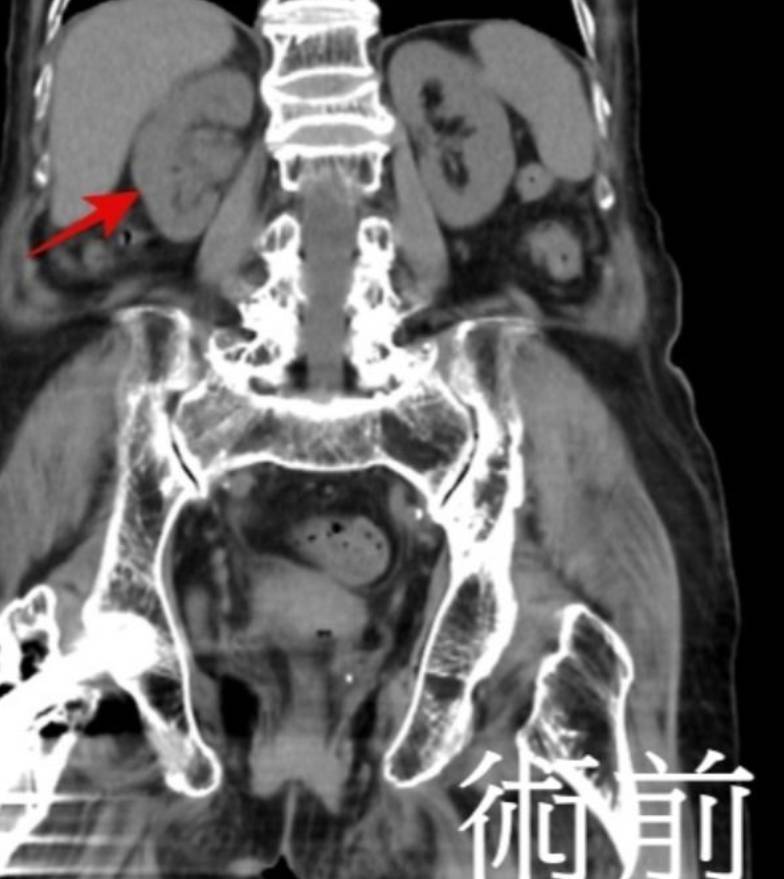

電腦斷層和核磁共振檢查結果顯示,祖母右側腎盂有腫瘤,且已侵犯到腎盂旁的脂肪,確診為第三期腎盂及輸尿管癌,幸好並未轉移到其他器官。然而祖母突然感染新冠肺炎合併肺積水緊急住院,所幸經過治療後成功脫離險境,體力也逐漸恢復。黃志平指出,經匯集多專科會診討論治療方案後,決定採用達文西機械人手臂手術切除右側腎臟、輸尿管和部分膀胱組織,期間一併修補右側疝氣,手術歷時210分鐘,出血量僅30毫升,毋須任何輸血,十分順利。

黃志平透露,術後阿月嬤可快速拔喉,毋須轉到加護病房觀察,在孫女的細心照顧下,其住院10天即順利出院,病理報告證實她罹患的是第三期腎盂泌尿道上皮癌。其後孫女每次都陪祖母覆診,又帶她去遊山玩水,追蹤2年來,不論是電腦斷層、磁振造影和膀胱鏡檢查均顯示腫瘤無任何復發跡象,可說是抗癌成功。